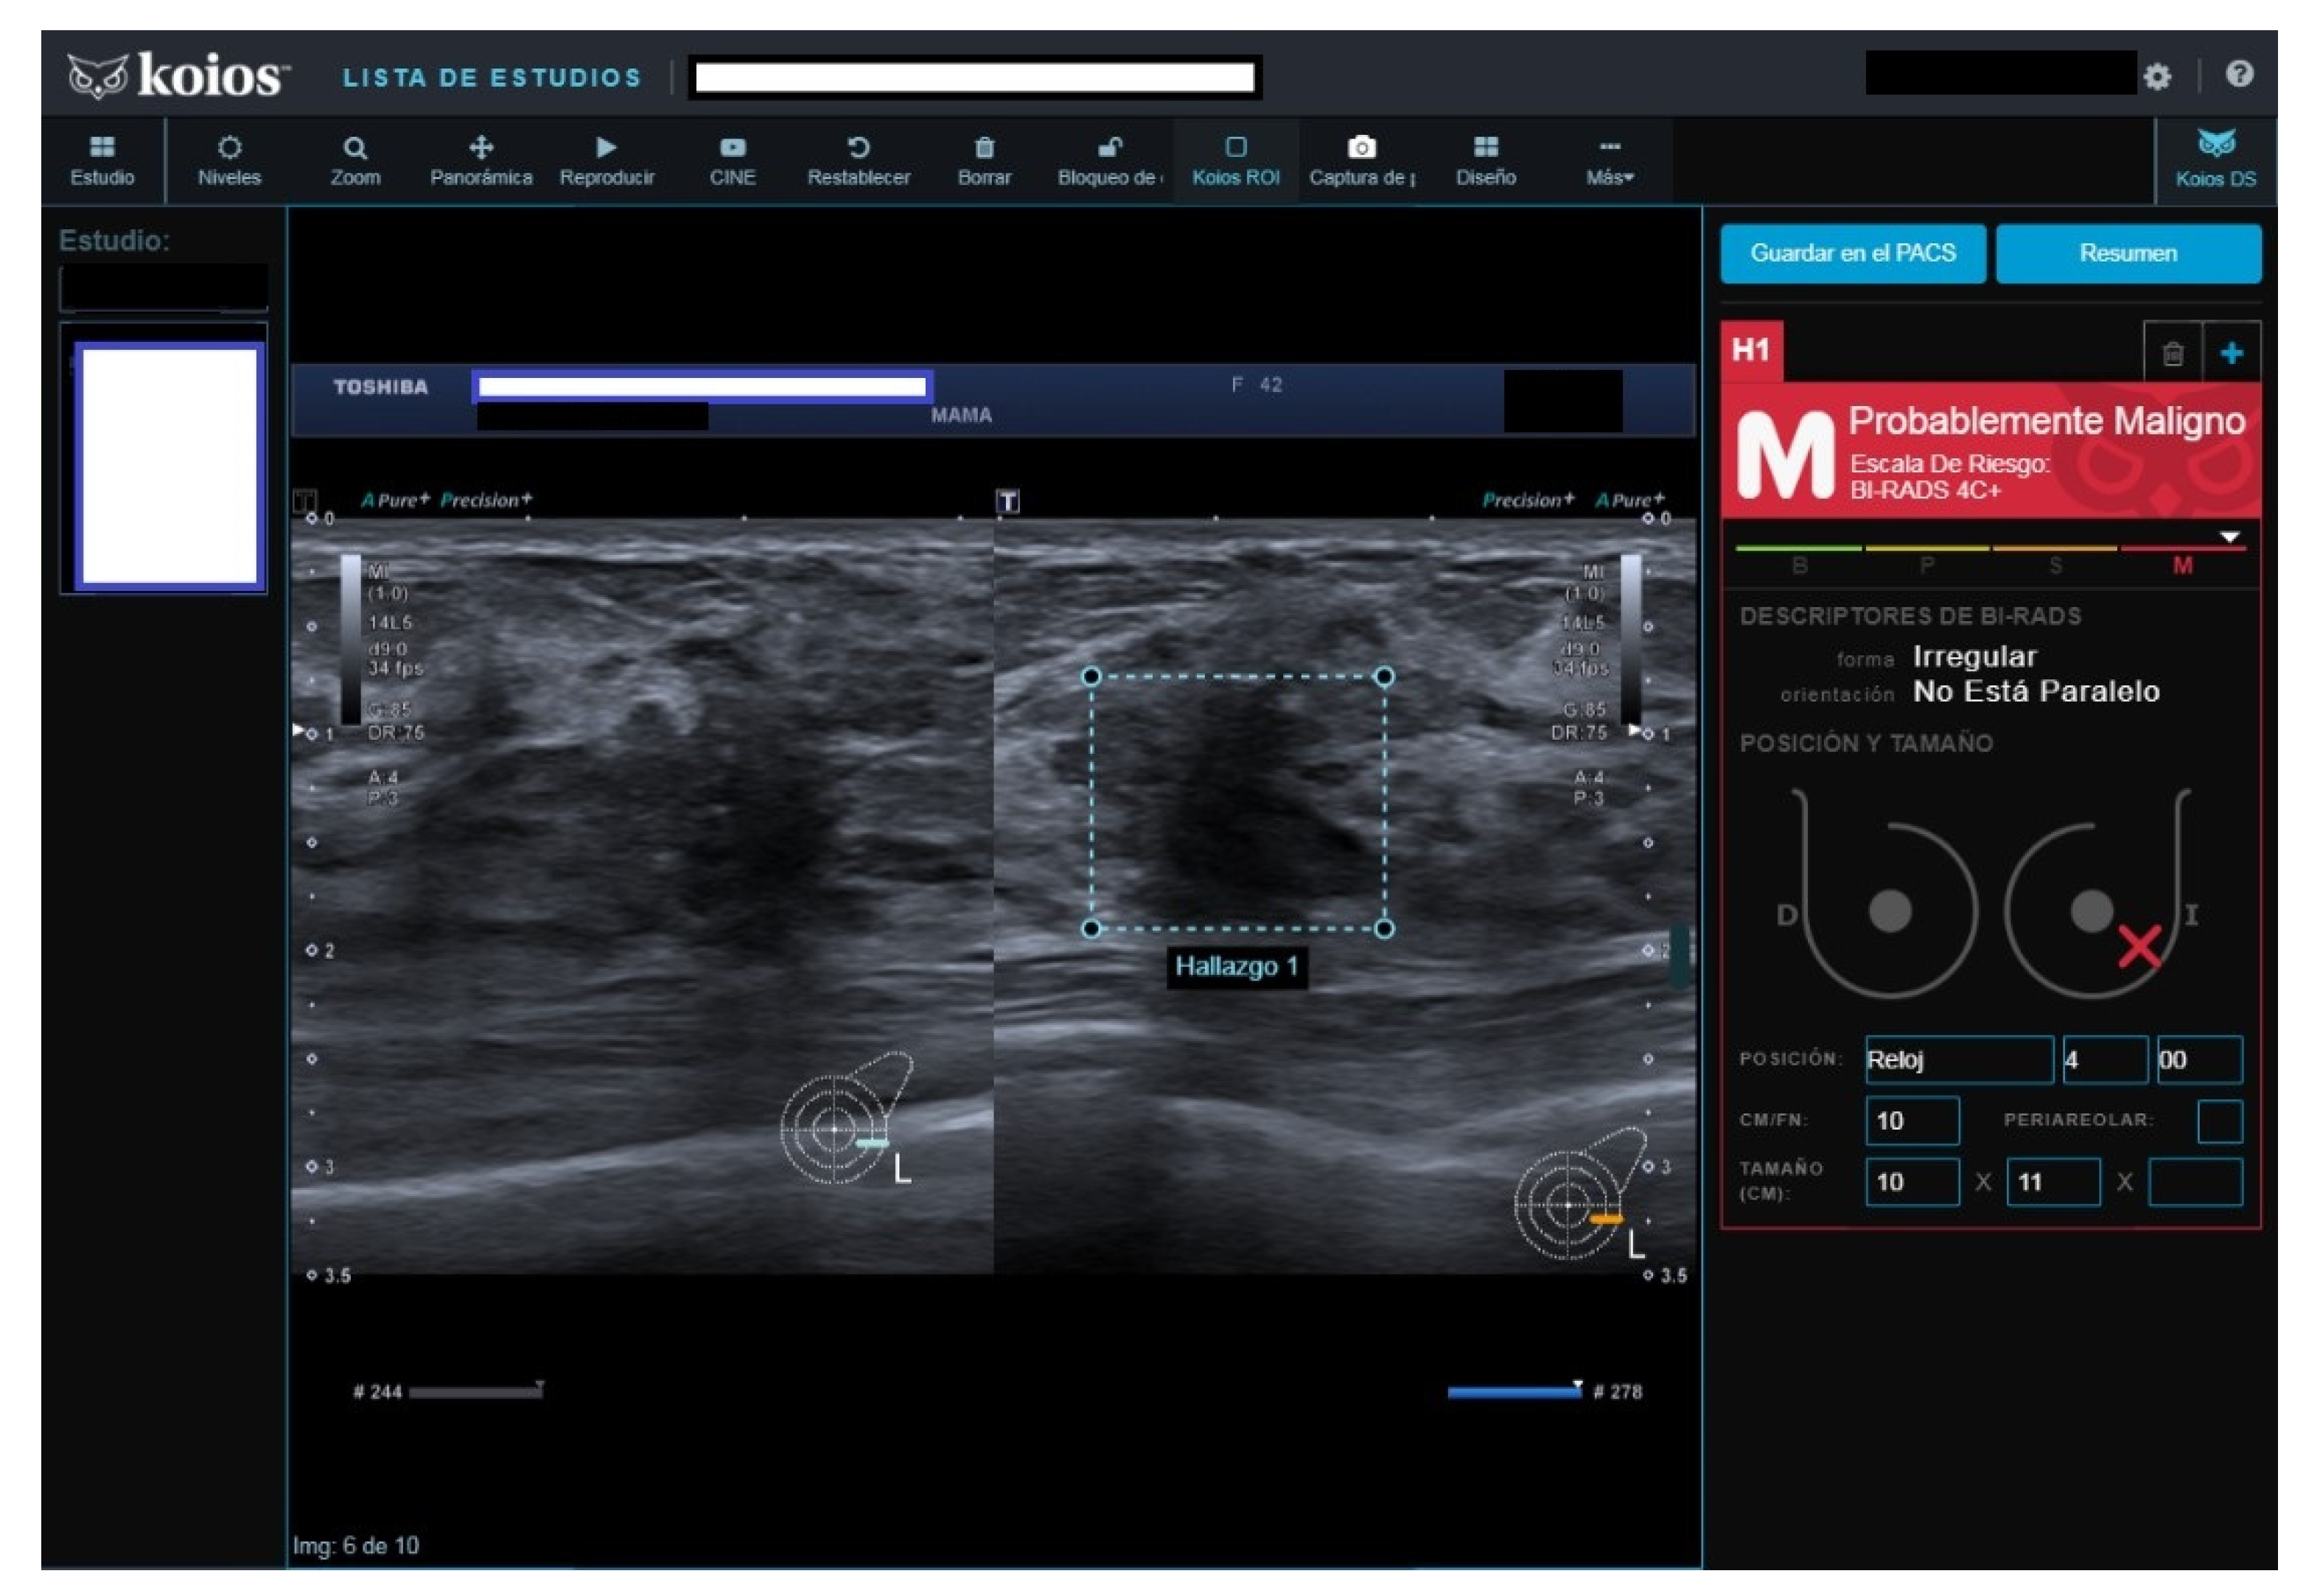

All four B2 cases had benign pathology results; a biopsy was performed for the following reasons after MCBP revision (B2 should not be biopsied): One had been core-biopsied 2 years previously, but due to the suspicious nature of the image, a wider vacuum-assisted biopsy was performed (Figure 2). The second had an unsuspicious scar from a previous malignant lumpectomy (micropapillary Ca), but because the patient presently had a cytologic papilloma diagnosis for nipple secretion, a new biopsy was performed. The third had a suspicious image from a previously benign biopsy (not performed at our institution) and previous studies with no obvious changes. Our MCBP recommended a new biopsy. The fourth had a suspicious mammography finding that was correlated with a benign-appearing BUS image. KOIOS reported cases one, two, and four as KPM and case three as Kpb.

Figure 2.

Suspicious image rated B2 by reader because of prior benign core biopsy (usual hyperplasia) and absence of change; rated KPM by KOIOS. Our multidisciplinary committee indicated a new and wider biopsy that was performed with US guidance and vacuum assistance. Pathology reported adenosis.